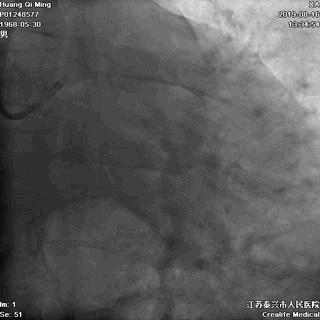

LCX植入后即刻效果满意

术后即刻效果满意